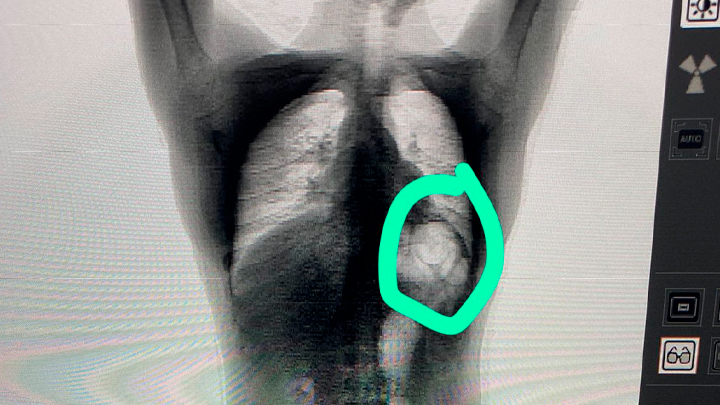

Ele foi levado até a Unidade Prisional Avançada de Itapema (Upa) para passar por um scanner, onde foi confirmado que ele engoliu os entorpecentes. Ele foi levado imediatamente para o hospital.